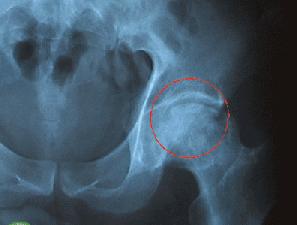

1.骨的原發性或轉移性腫瘤是病理性骨折最常見的原因,特別是溶骨性的原發或轉移性骨腫瘤。原發性骨腫瘤如多發性骨髓瘤、骨巨細胞瘤及溶骨性成骨肉瘤等;屬於轉移性骨腫瘤的如轉移性腎癌、乳腺癌、肺癌、甲狀腺癌及神經母細胞瘤等。不少原發性和轉移性骨腫瘤有時因病理性骨折後才被發現。

病理性骨折損傷2、對局部良性腫瘤所致者,可行腫瘤切除(或刮除)加植骨術,腫瘤範圍廣泛者則需行截除術,並酌情考慮修補性手術。

3、因惡性腫瘤所致者,如全身無轉移,可根據腫瘤的性質、病程、分期及全身與局部情況酌情行廣泛性或根治性手術。對已有全身轉移者,可考慮選用藥物或放射療法,局部予以適當固定,以減少患者痛苦。